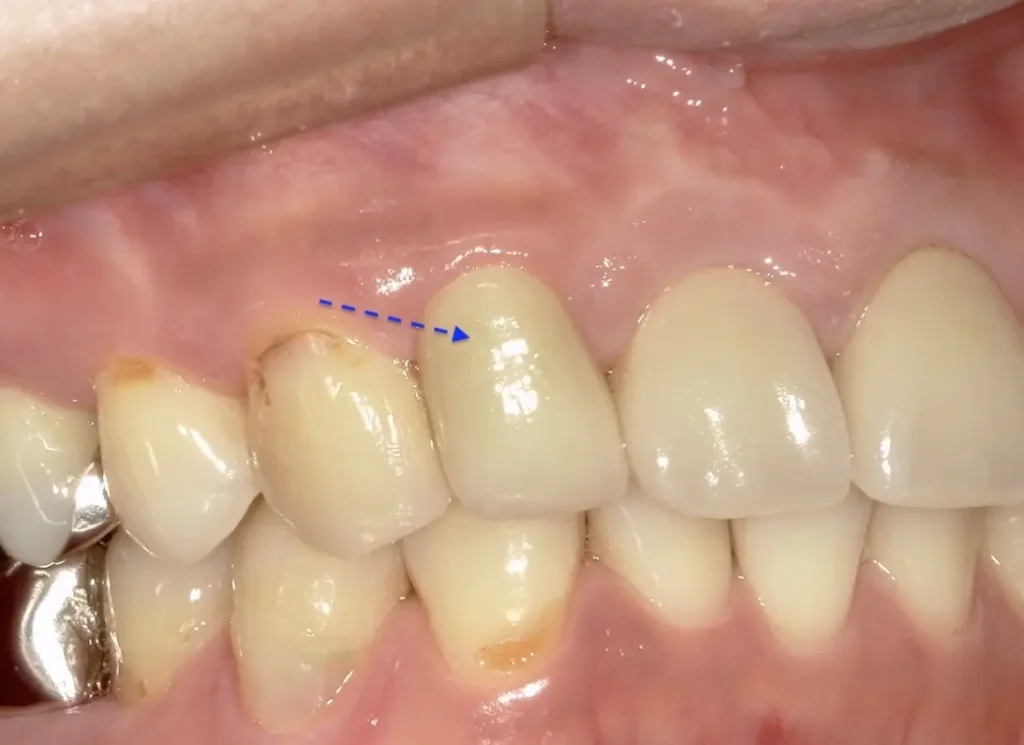

症状はすべて改善、経過2年後

術後

症状もレントゲン上の炎症も全く再発はありません

口腔内写真

向かって奥から2番目審美性も機能も維持されています